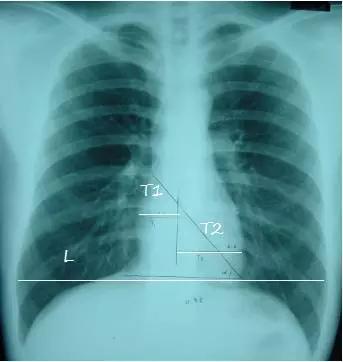

5、心影位置及大小

T1:心脏最右缘至前正中线距离

T2:心脏最左缘至前正中线距离

L :通过膈肌顶部至两侧胸廓内沿并平行于膈肌的线

心胸比 = (T1+T2) / L

- 正常<= 0.50

- 轻度增大 0.51-0.55

- 中度增大 0.56-0.60

- 重度增大 >= 0.60